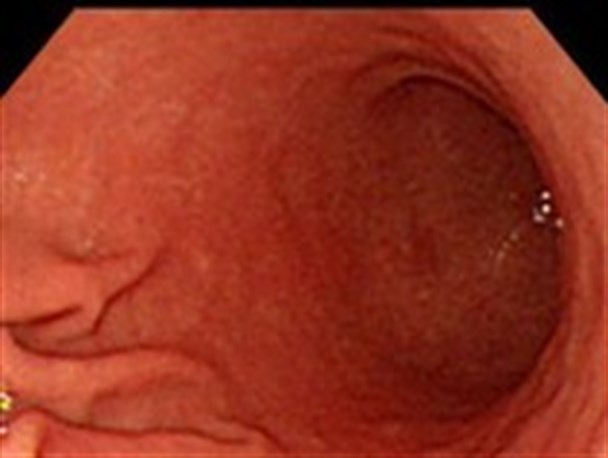

یک متخصص داخلی گفت: نامناسب بودن رژیم غذایی، وجود نیتریت‌ها، مصرف فست فود، نمک فراوان و الکل، کشیدن سیگار و استرس شدید از عوامل سرطان معده هستند.

وی افزود: از هر هزار نفر به ظاهر سالم وقتی آزمایش آندوسکوپی انجام داده‌اند حدود ۳۴ درصد افراد مبتلا به گاستریت معده بوده‌اند.

این متخصص داخلی سرطان معده را شایع‌ترین سرطان در آقایان دانست و افزود: متاسفانه در کشور ما سرطان معده، شایع‌ترین سرطان دستگاه گوارش در آقایان است که در این چند سال اخیر برخلاف کشور‌های دیگر، افزایش چشمگیری داشته است.

زمان‌زاده ادامه داد: اصلیترین عامل ابتلا به سرطان معده، نوعی میکروب به نام هلیکوباک‌تر بوده و در اغلب کسانی که مبتلا به سرطان معده بوده‌اند مشاهده شده است.

وی با اشاره به عوامل دیگر سرطان معده گفت: نامناسب بودن رژیم غذایی، وجود نیترت‌ها، مصرف از فست فود، نمک فراوان، مصرف الکل، کشیدن سیگار و استرس شدید از دیگر عوامل سرطان معده است.

این متخصص داخلی در مورد علایم وجود میکروب معده در بدن گفت: احساسی پر بودن شکم، بوی بد دهان، مدفوع سیاه، کاهش وزن، زخم معده، تهوع و استفراغ علایمی است که احتمال التهاب مخاط معده را در بدن مطرح می‌کند، در این حالت میکروب گاستریت داخل بدن شده است که با انجام یک‌سری آزمایشات پزشک تشخیص نهایی را می‌دهد.

زمان‌زاده درباره از بین بردن و درمان میکروب هلیکوباک‌تر اظهار کرد: اگر در آزمایش خون و مدفوع یا آندوسکوپی بیمار، میکروب هلیکوباک‌تر دیده شود برای بیمار آنتی بیوتیک تجویز می‌شود.